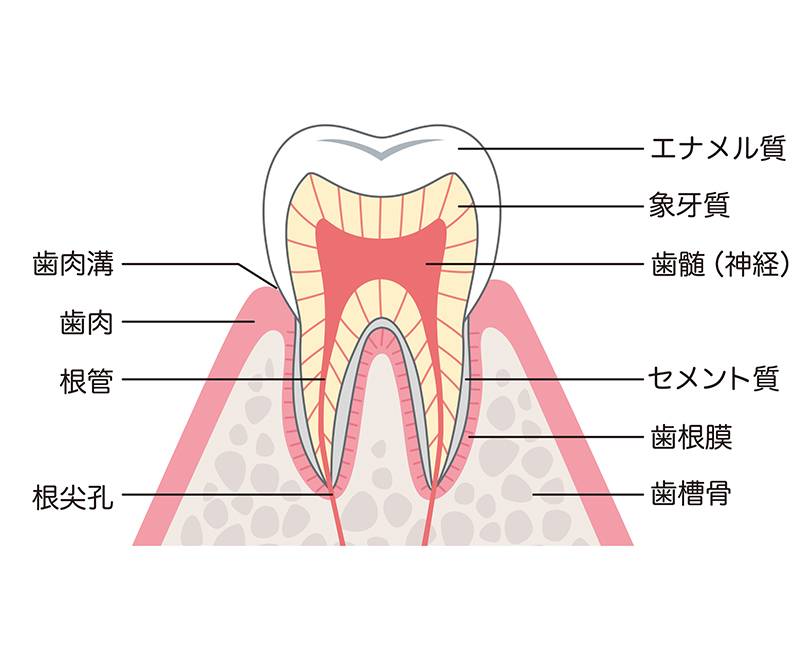

白くなるメカニズムをご説明する前に、まずは歯の構造からご説明します。歯は、表面の『エナメル質』、その内側に黄褐色の『象牙質』、さらに深部の『歯髄』(神経部)で構成されています。エナメル質は人体で最も硬質な組織で、ほとんどが無機質で構成されています。しかしわずかな有機質が含まれており、その有機質の着色が歯の変色となります。また、いくら硬質でも年齢とともにすり減り、代わりに内部にある象牙質が厚みを増すことによって歯の黄ばみが発生します。

白くなるメカニズムをご説明する前に、まずは歯の構造からご説明します。歯は、表面の『エナメル質』、その内側に黄褐色の『象牙質』、さらに深部の『歯髄』(神経部)で構成されています。エナメル質は人体で最も硬質な組織で、ほとんどが無機質で構成されています。しかしわずかな有機質が含まれており、その有機質の着色が歯の変色となります。また、いくら硬質でも年齢とともにすり減り、代わりに内部にある象牙質が厚みを増すことによって歯の黄ばみが発生します。